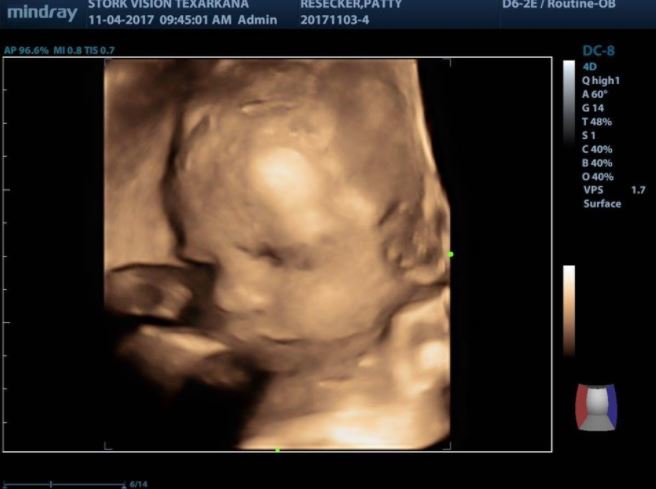

這段求子之路走得相當艱辛,受孕的過程也不是一次就成功,三人經過漫長且反覆的測試、研究和懷疑,2017年5月,帕蒂才終於成功植入胚胎!

當時兒子和媳婦告訴帕蒂她終於懷孕時,帕蒂還激動到當場哭泣,三人擁抱在一起互相安慰和激勵,場面既溫馨又讓人心疼。

一家人還特地拍攝帕蒂懷孕的照片,為這個全家殷殷期盼的奇蹟留下一輩子的紀念。

帕蒂的孕期總共維持7個月,最後她接受剖腹手術,順利產下孫子克羅斯(Kross Allen Jones),這個健康的男寶寶彷彿天使降臨,讓這家人洋溢著幸福和滿足,想必這5年來的辛苦都值得了!